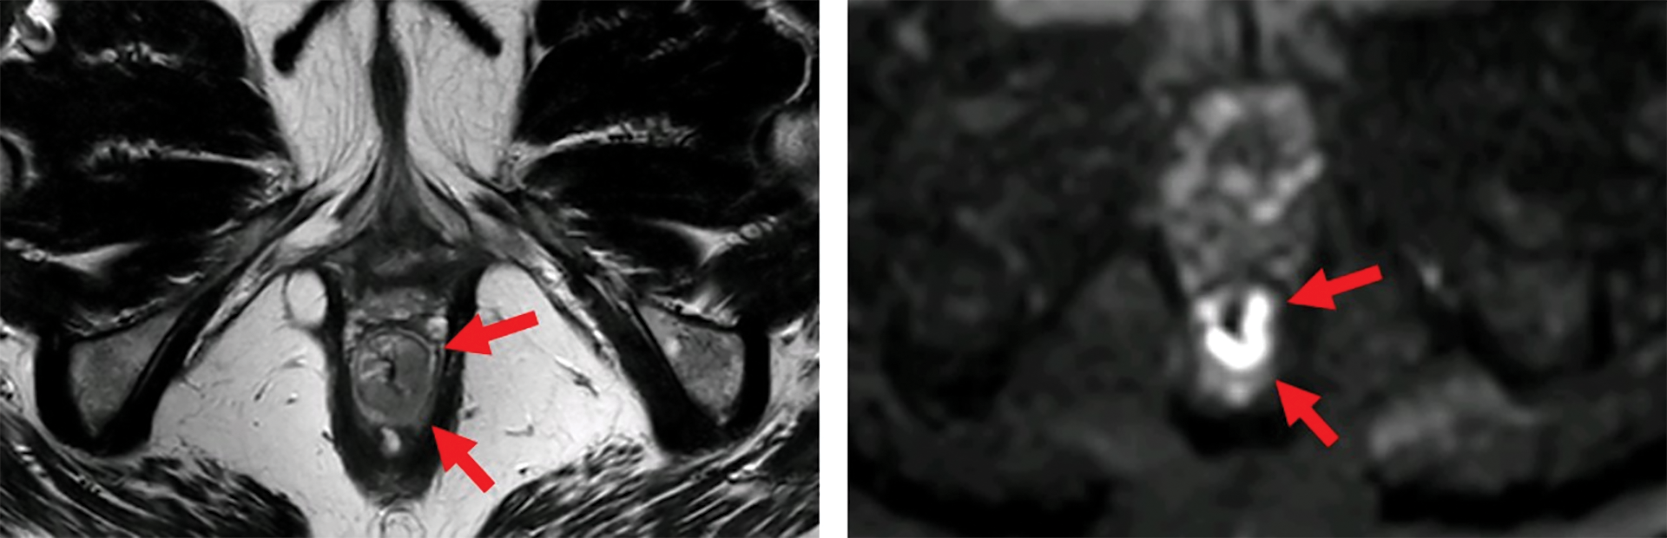

Figure 1

MRI before (top) and after (bottom) neoadjuvant therapy. Axial T2‑weighted and b1000 DWI images show a distal rectal tumor (red arrows). After neoadjuvant therapy, a T2 dark, fibrotic remnant is seen without restricted diffusion (green arrows), indicative of a clinical complete response.